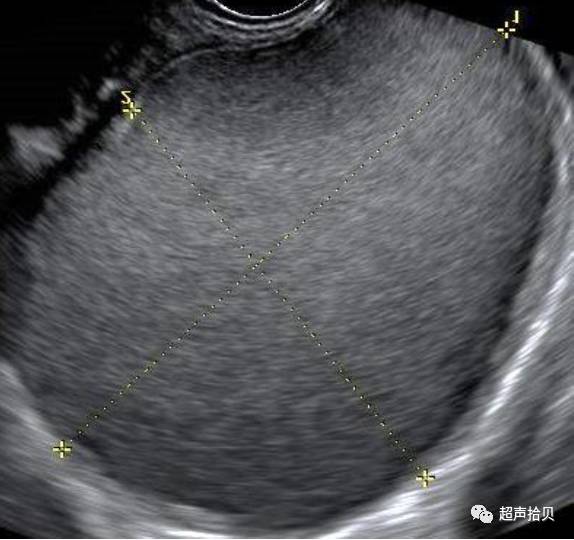

卵巢子宫内膜异位囊肿通常伴随其他子宫内膜异位病变,如粘连,深部浸深部浸润性内异症。卵巢亲吻征( ‘kissing’ ovaries sign,图S2)提示存在严重的盆腔粘连。存在kissing sign的病人,异位症累及肠管、输卵管的概率分别为18.5% 、92.6%,普通患者分别为2.5% 33%。

图S2显示“亲吻”卵巢的超声图像标志:包含子宫内膜异位症的两个卵巢通过道格拉斯囊中的粘连相互固定